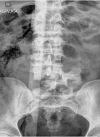

Traumatic L5 Posterolateral Spondyloptosis: A Case Report and Review of the Literature

Traumatic retrolisthesis of the lumbar spine is a rare clinical entity. Only a few case reports have shown retrolisthesis of the fractured fragment over the inferior vertebral body. Fracture dislocations of the spine are unstable injuries that require operative fixation to restore alignment and prevent progressive deformity. We present the case of a traumatic L5-S1 fracture dislocation with retrolisthesis of the L5 vertebral body over the superior aspect of S1 managed with anterior, middle, and posterior column reconstruction. The patient presented with paraplegia and bowel and bladder incontinence. Retrolisthesis fracture dislocations injuries are rare, and as such, there are no guidelines regarding their management. In our case, we performed an L5 vertebrectomy with anterior, middle, and posterior column reconstruction via a posterior approach using a lumbosacral-pelvic construct. The patient did not regain function in his distal lower extremities postoperatively.